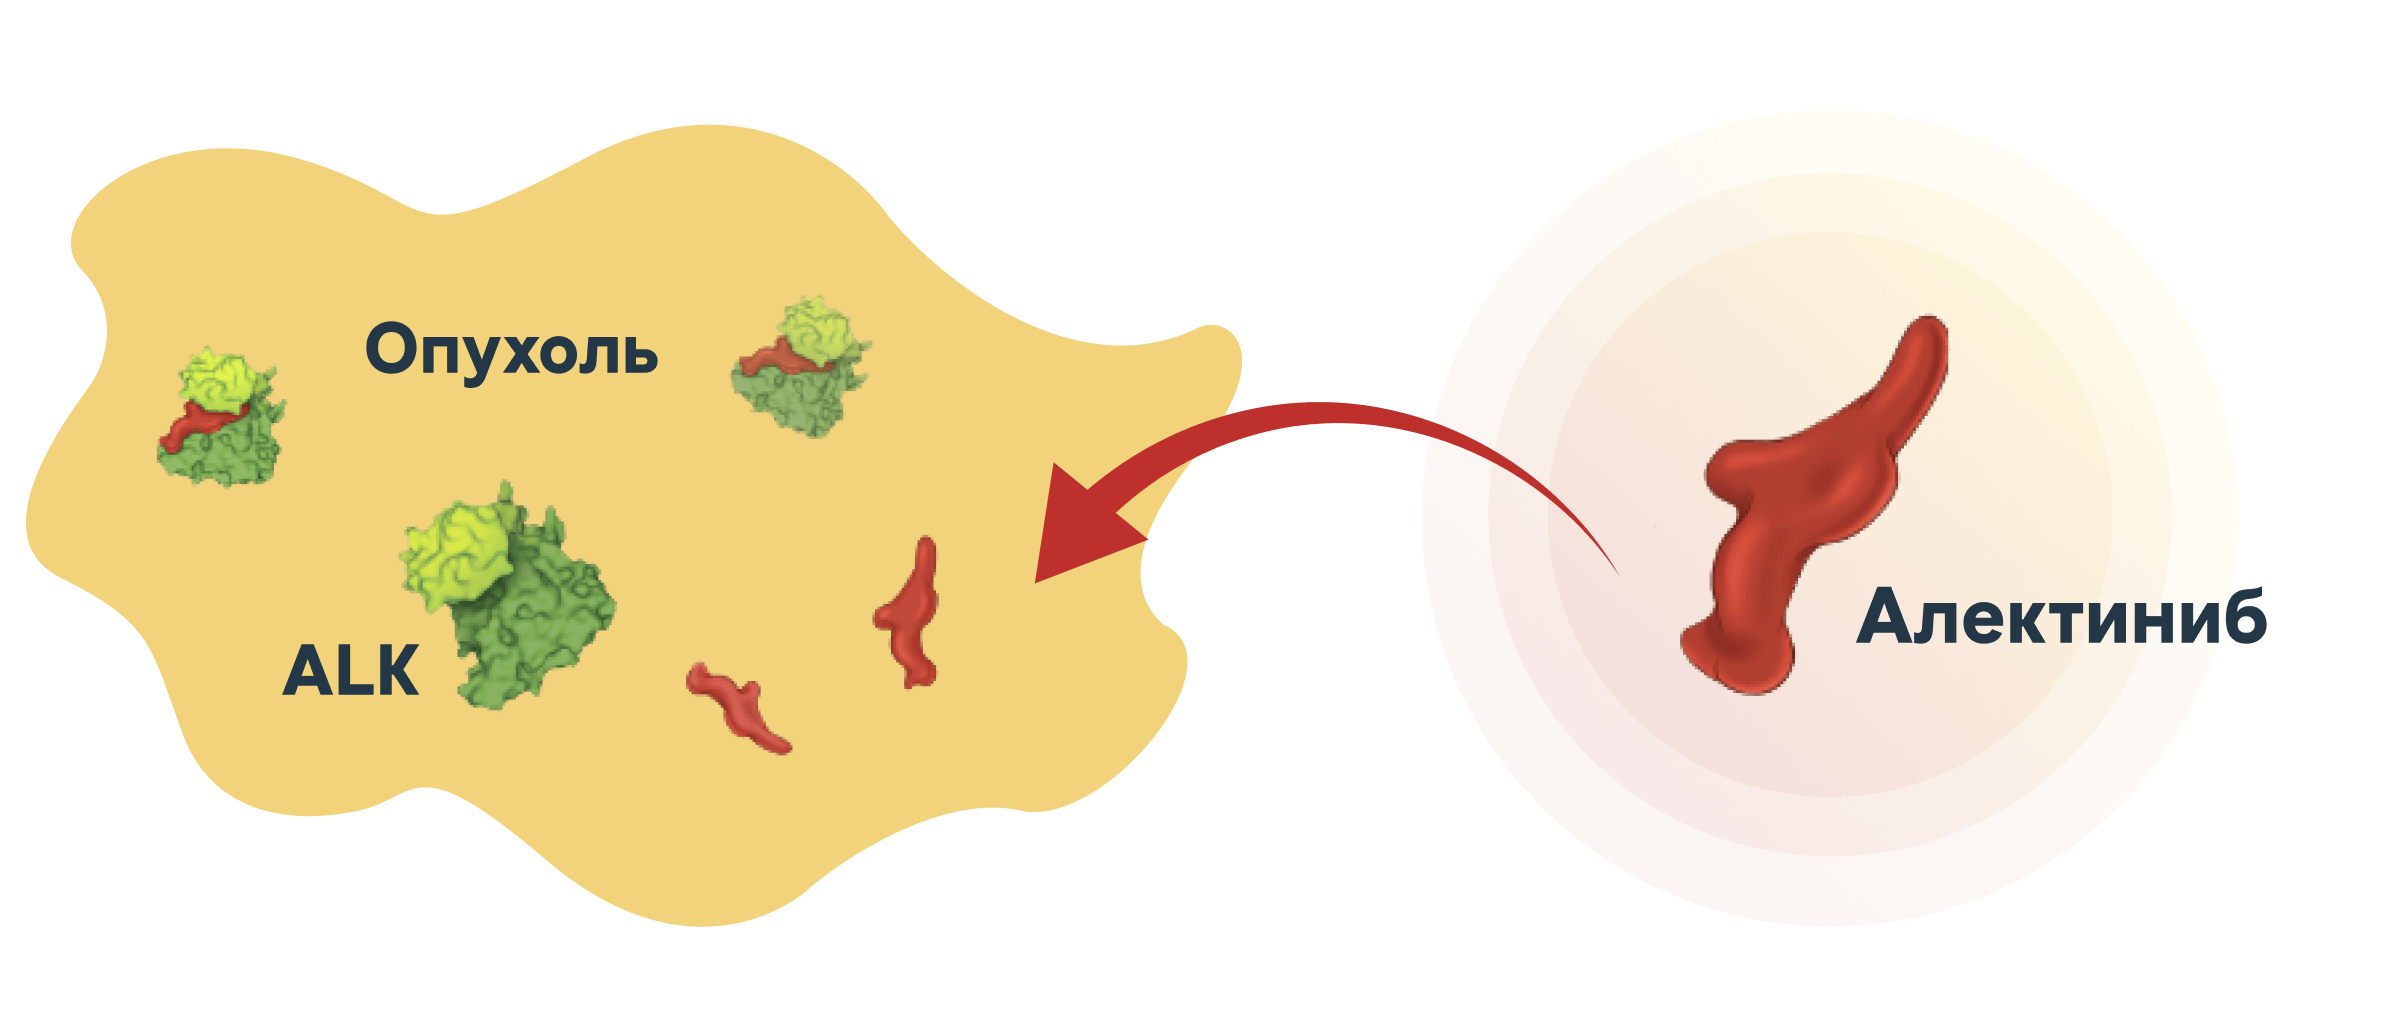

это ингибитор тирозинкиназы, используемый в лечении ALK-позитивного немелкоклеточного рака лёгкого (НМРЛ).

Алектиниб блокирует аномальную активность ALK-белка, который стимулирует рост и деление опухолевых клеток1,2.

Алектиниб воздействует на ALK+ НМРЛ системно и в ЦНС

Предлагаемый механизм действия Алектиниба1,2